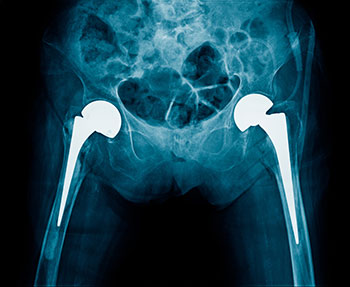

This clinical practice guideline is intended for use with adult patients (ages 18 years and older) who have been diagnosed by a trained healthcare provider with osteoarthritis of the hip and are undergoing treatment.

Total Hip Arthroplasty Toolkit